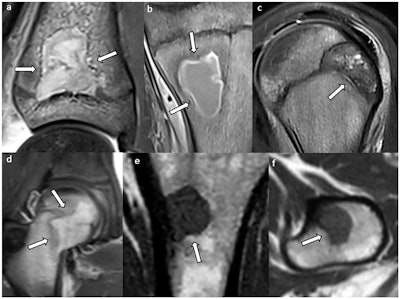

Lesions with concave borders (arrows): (a, b) intraosseous abscess, (c) chondroblastoma, (d) Langerhans cell histiocytosis, and (e, f) metastasis (same patient). In (a) and (c), one concave border follows the shape of the growth plate.Kalaaji et al; Insights Into Imaging

All osteonecrosis lesions, 44.8% of fibrous dysplasia lesions, 20.8% of abscesses, 14.8% of chondroblastomas, 12.5% of Langerhans cell histiocytosis lesions, and 2.9% of metastases showed at least two concave margins. No lesions in the other groups had more than one concave margin.